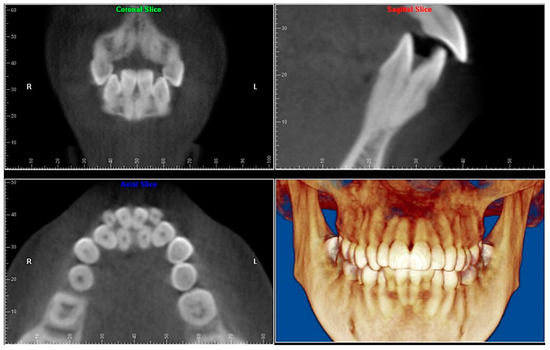

- Evaluation of impacted teeth, a common indication of CBCT in orthodontics. The advantages of CBCT include assessment of the tooth location and position, the stage of development, and status of adjacent teeth. CBCT is justified in these cases, because CBCT has the capability of evaluating the impacted teeth and adjacent structures more accurately than 2D conventional imaging. The benefit–risk ratio is favorable, especially if the CBCT volume is collimated to the impacted tooth. Figure 1, Figure 2, Figure 3 and Figure 4 show an example of impacted maxillary canines, and their proximity to the maxillary lateral incisors. Figure 1 shows an intraoral photograph. The benefit of CBCT acquisition in this case includes the ability to visualize the canines and the lateral incisors in three dimensions, which can be visualized in Figure 2 and Figure 3. In this case, the maxillary right lateral incisor exhibited external root resorption, a finding that would be difficult to see on a conventional 2D panoramic radiograph. Figure 4 shows a Maximum Intensity Projection of a panoramic view derived from the CBCT volume. This unique view is free of magnification, distortion, ghost images, and overlaps frequently seen in conventional 2D panoramic radiography.